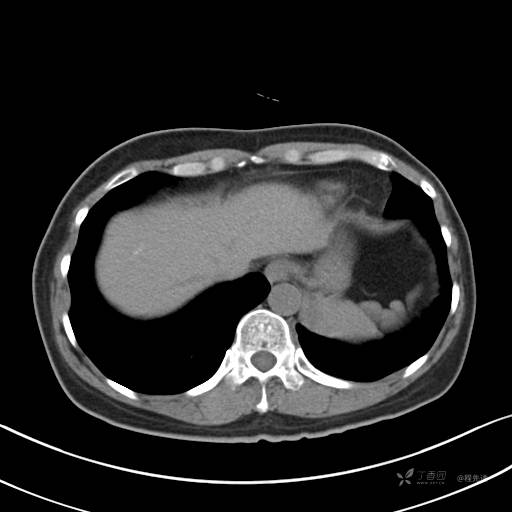

冠状位重建

CT值:平扫:31HU,动脉期:74HU,静脉期:84HU